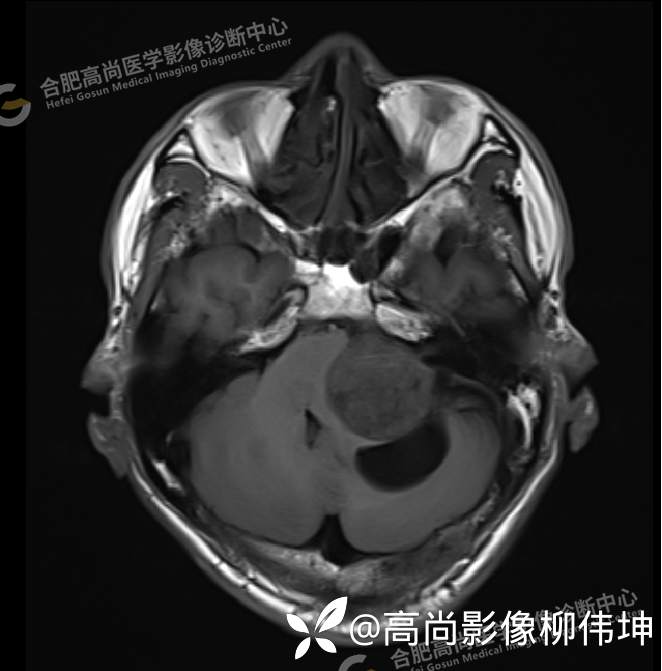

T1WI-tra

颅脑MRI平扫+增强示:双侧大脑半球对称,左侧桥小脑角区可见一团块状异常信号影,边界尚清,病灶与小脑幕宽基底附着呈“D”字征,上缘指状伸入幕缘上生长,病灶大小约43mmx42mmx36mm,其内信号不均,T1WI呈等低信号,T2WI呈混杂等高信号;FLAIR呈高信号,内可见条状低信号影,DWI呈稍高信号,ADC呈低信号,弥散轻度受限,病灶后方左侧小脑半球区可见一大小约33mmx16mm的弧形长T1长T2信号影,FLAIR呈低信号,其周围可见片状高信号影,相邻桥小脑角增宽。脑桥、小脑蚓部,小脑半球、第四脑室、环池受压变形,向右侧偏移,四脑室明显变窄,增强扫描病灶可见不均匀明显强化,邻近脑膜可见线样强化改变。其后方囊性灶未见异常强化。邻近骨质未见明显异常信号。左侧内听道显示正常;左侧中耳乳突内可见不规则性长T1长T2信号影。余脑实质内未见局灶性信号异常。双侧侧脑室及第三脑室体积增大,中线结构居中。矢状面示垂体形态大小正常,未见局灶性异常信号。

1.左侧桥小脑角区占位伴周围囊变,轻度梗阻性脑积水;考虑左小脑幕脑膜瘤。